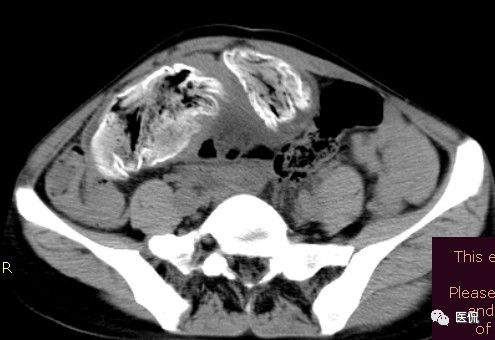

女 40岁 ,10年前做个剖腹产术。之后到现在一直感觉肚子疼,去很多医院做检查 诊断肠结核,经过反复抗结核治疗。病人10年瘦了几十斤。

腹腔内残留的纱布在人体内引起渗出或液化坏死并纤维包裹形成异物性脓肿(纱布瘤)。纱布瘤的影像特点:圆形或卵圆形肿块,较大,有完整包膜,薄壁,较少的情况下为厚壁,边界较完整,增强后薄膜可以持续强化。不同时期的纱布瘤可以有不同表现:早期(10个月或半年内)多表现为蜂窝状;2~5年内一般表现为囊性飘带状;10~20年之后则为实性软组织密度,包膜钙化呈钙化网状结构。手术过程中残留在人体内的医用纱布所形成的肿瘤样病变。